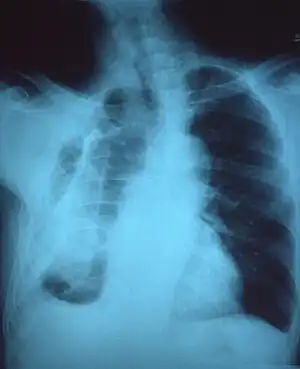

CXR of an individual affected by fibrothorax (consequence of tuberculosis)

Extensive left-sided fibrothorax

Chest radiograph displaying inhomogeneous opacification of the left half of the chest that is fibrothorax